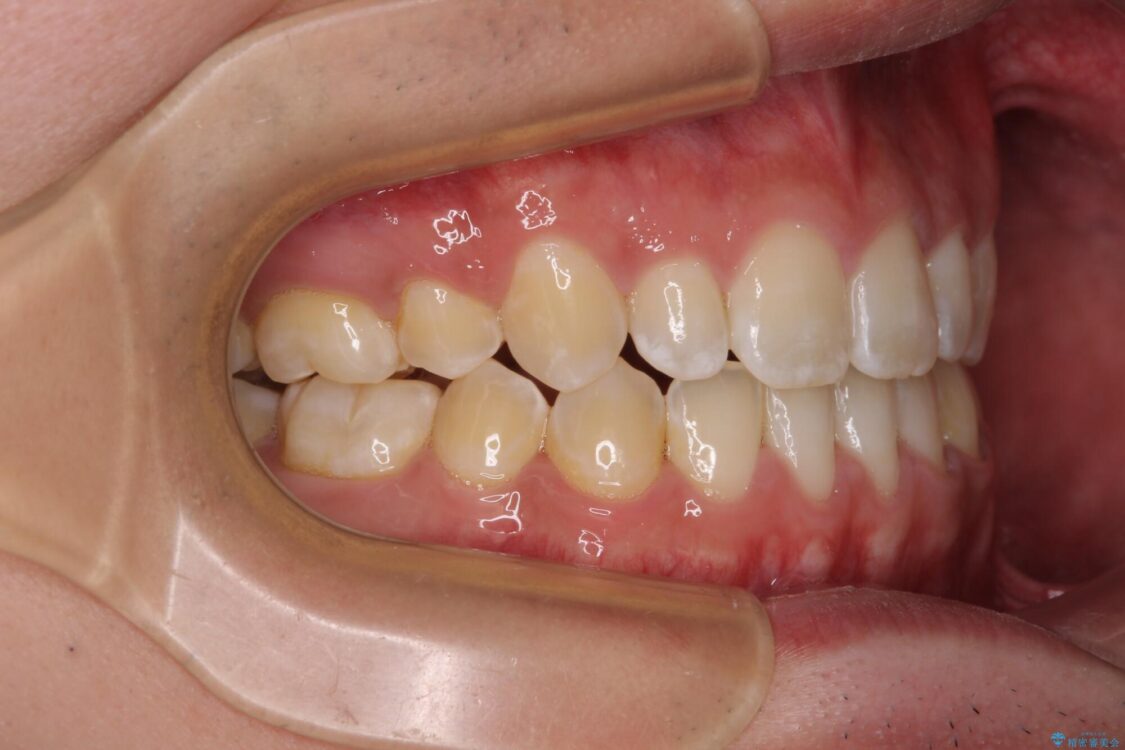

治療途中

• 口元の突出感を改善 受け口傾向の咬み合わせの抜歯矯正 治療途中画像